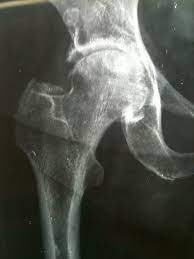

Per diagnosticare l’artrosi degenerativa dell’anca e soprattutto per classificarla è necessaria una radiografia nelle due posizioni standard: antero posteriore di bacino e assiale di anca. Questo esame serve ad evidenziare i quattro segni radiologici fondamentalidell’artrosi:

- riduzione della rima articolare

- addensamento dell’osso subcondrale

- geodi (cavitazioni dell’osso)

- osteofiti